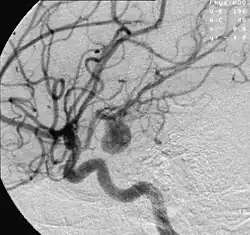

![]() | |

| Angiography of an aneurysm in a brain artery. The aneurysm is the large bulge in the center of the image. | |

There are currently two treatment options for brain aneurysms: surgical clipping or endovascular coiling. There is currently debate in the medical literature about which treatment is most appropriate given particular situations.[41]

Endovascular coiling was introduced by Italian neurosurgeon Guido Guglielmi at UCLA in 1989. It consists of passing a catheter into the femoral artery in the groin, through the aorta, into the brain arteries, and finally into the aneurysm itself. Platinum coils initiate a clotting reaction within the aneurysm that, if successful, fills the aneurysm dome and prevents its rupture.[42] A flow diverter can be used, but risks complications.[43]